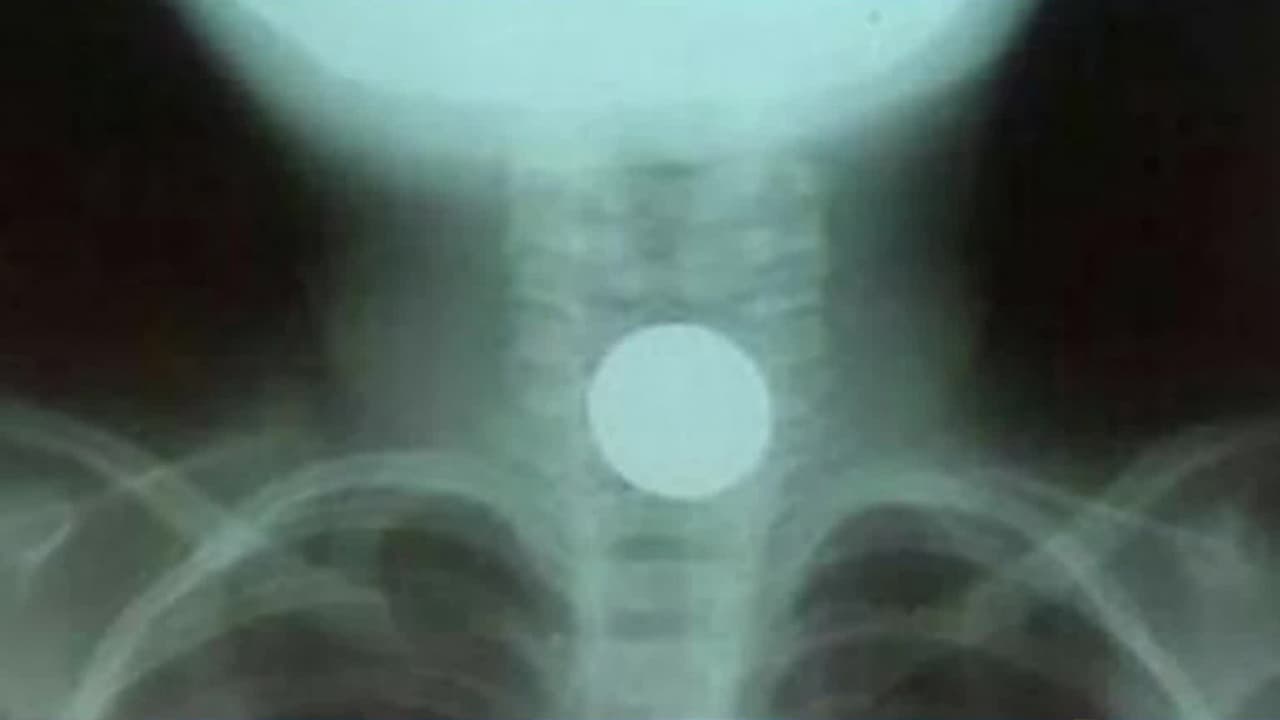

Una travesura casi le cuesta la vida a esta niña que estuvo a punto de asfixiarse con una moneda

La pequeña de solo 4 años se tragó la moneda, que se le quedó atascada en la garganta. Los médicos no conseguían sacársela y casi muere asfixiada.